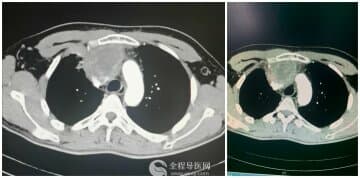

患者庞某,男,68岁,2010年6月因“头痛、视物模糊4年、加重伴嗜睡1月”入住徐医附院神经外科,经头颅MR检查示“鞍区巨大肿瘤,包绕两侧颈内动脉”,最大直径达8cm,告知手术风险极大,且不能全切,费用高昂,患者家属考虑再三,决定试行伽马刀治疗。

治疗后患者嗜睡症状逐步好转。2月后患者复查头颅MR,已治疗区病灶强化程度较前明显下降,予二次伽马刀治疗。治疗后定期随访,患者头痛、视力下降等症状逐步改善。2011年10月底患者再次复查头颅MR,奇迹出现了,瘤体已惊险缩小,局部最大径已不足3cm。因贴近视交叉处仍有少量病灶残留,李忠喜主任详细评估病人病情,与家属充分沟通后决定予第三次伽马刀治疗控制局部残留病灶。目前患者治疗结束,状态良好,无头痛、明显视力障碍等不适。